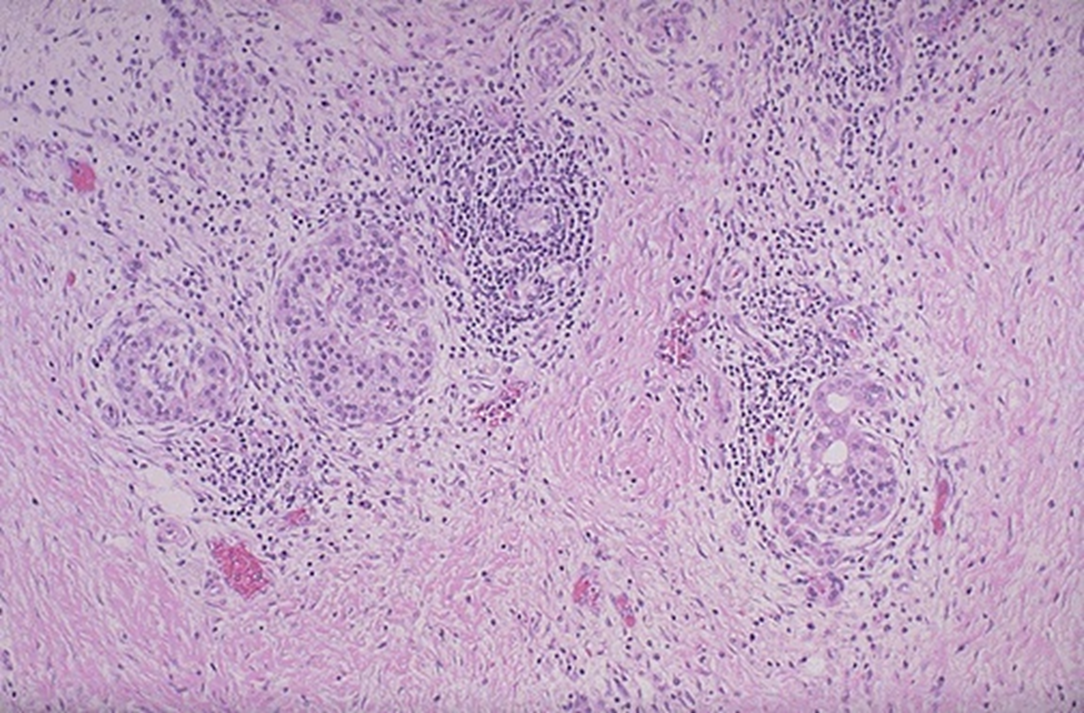

panc adenocarcinoma.

poorly differentiated glands and extensive desmoplasia (collagenous stroma)

pancreatic adenocarcinoma